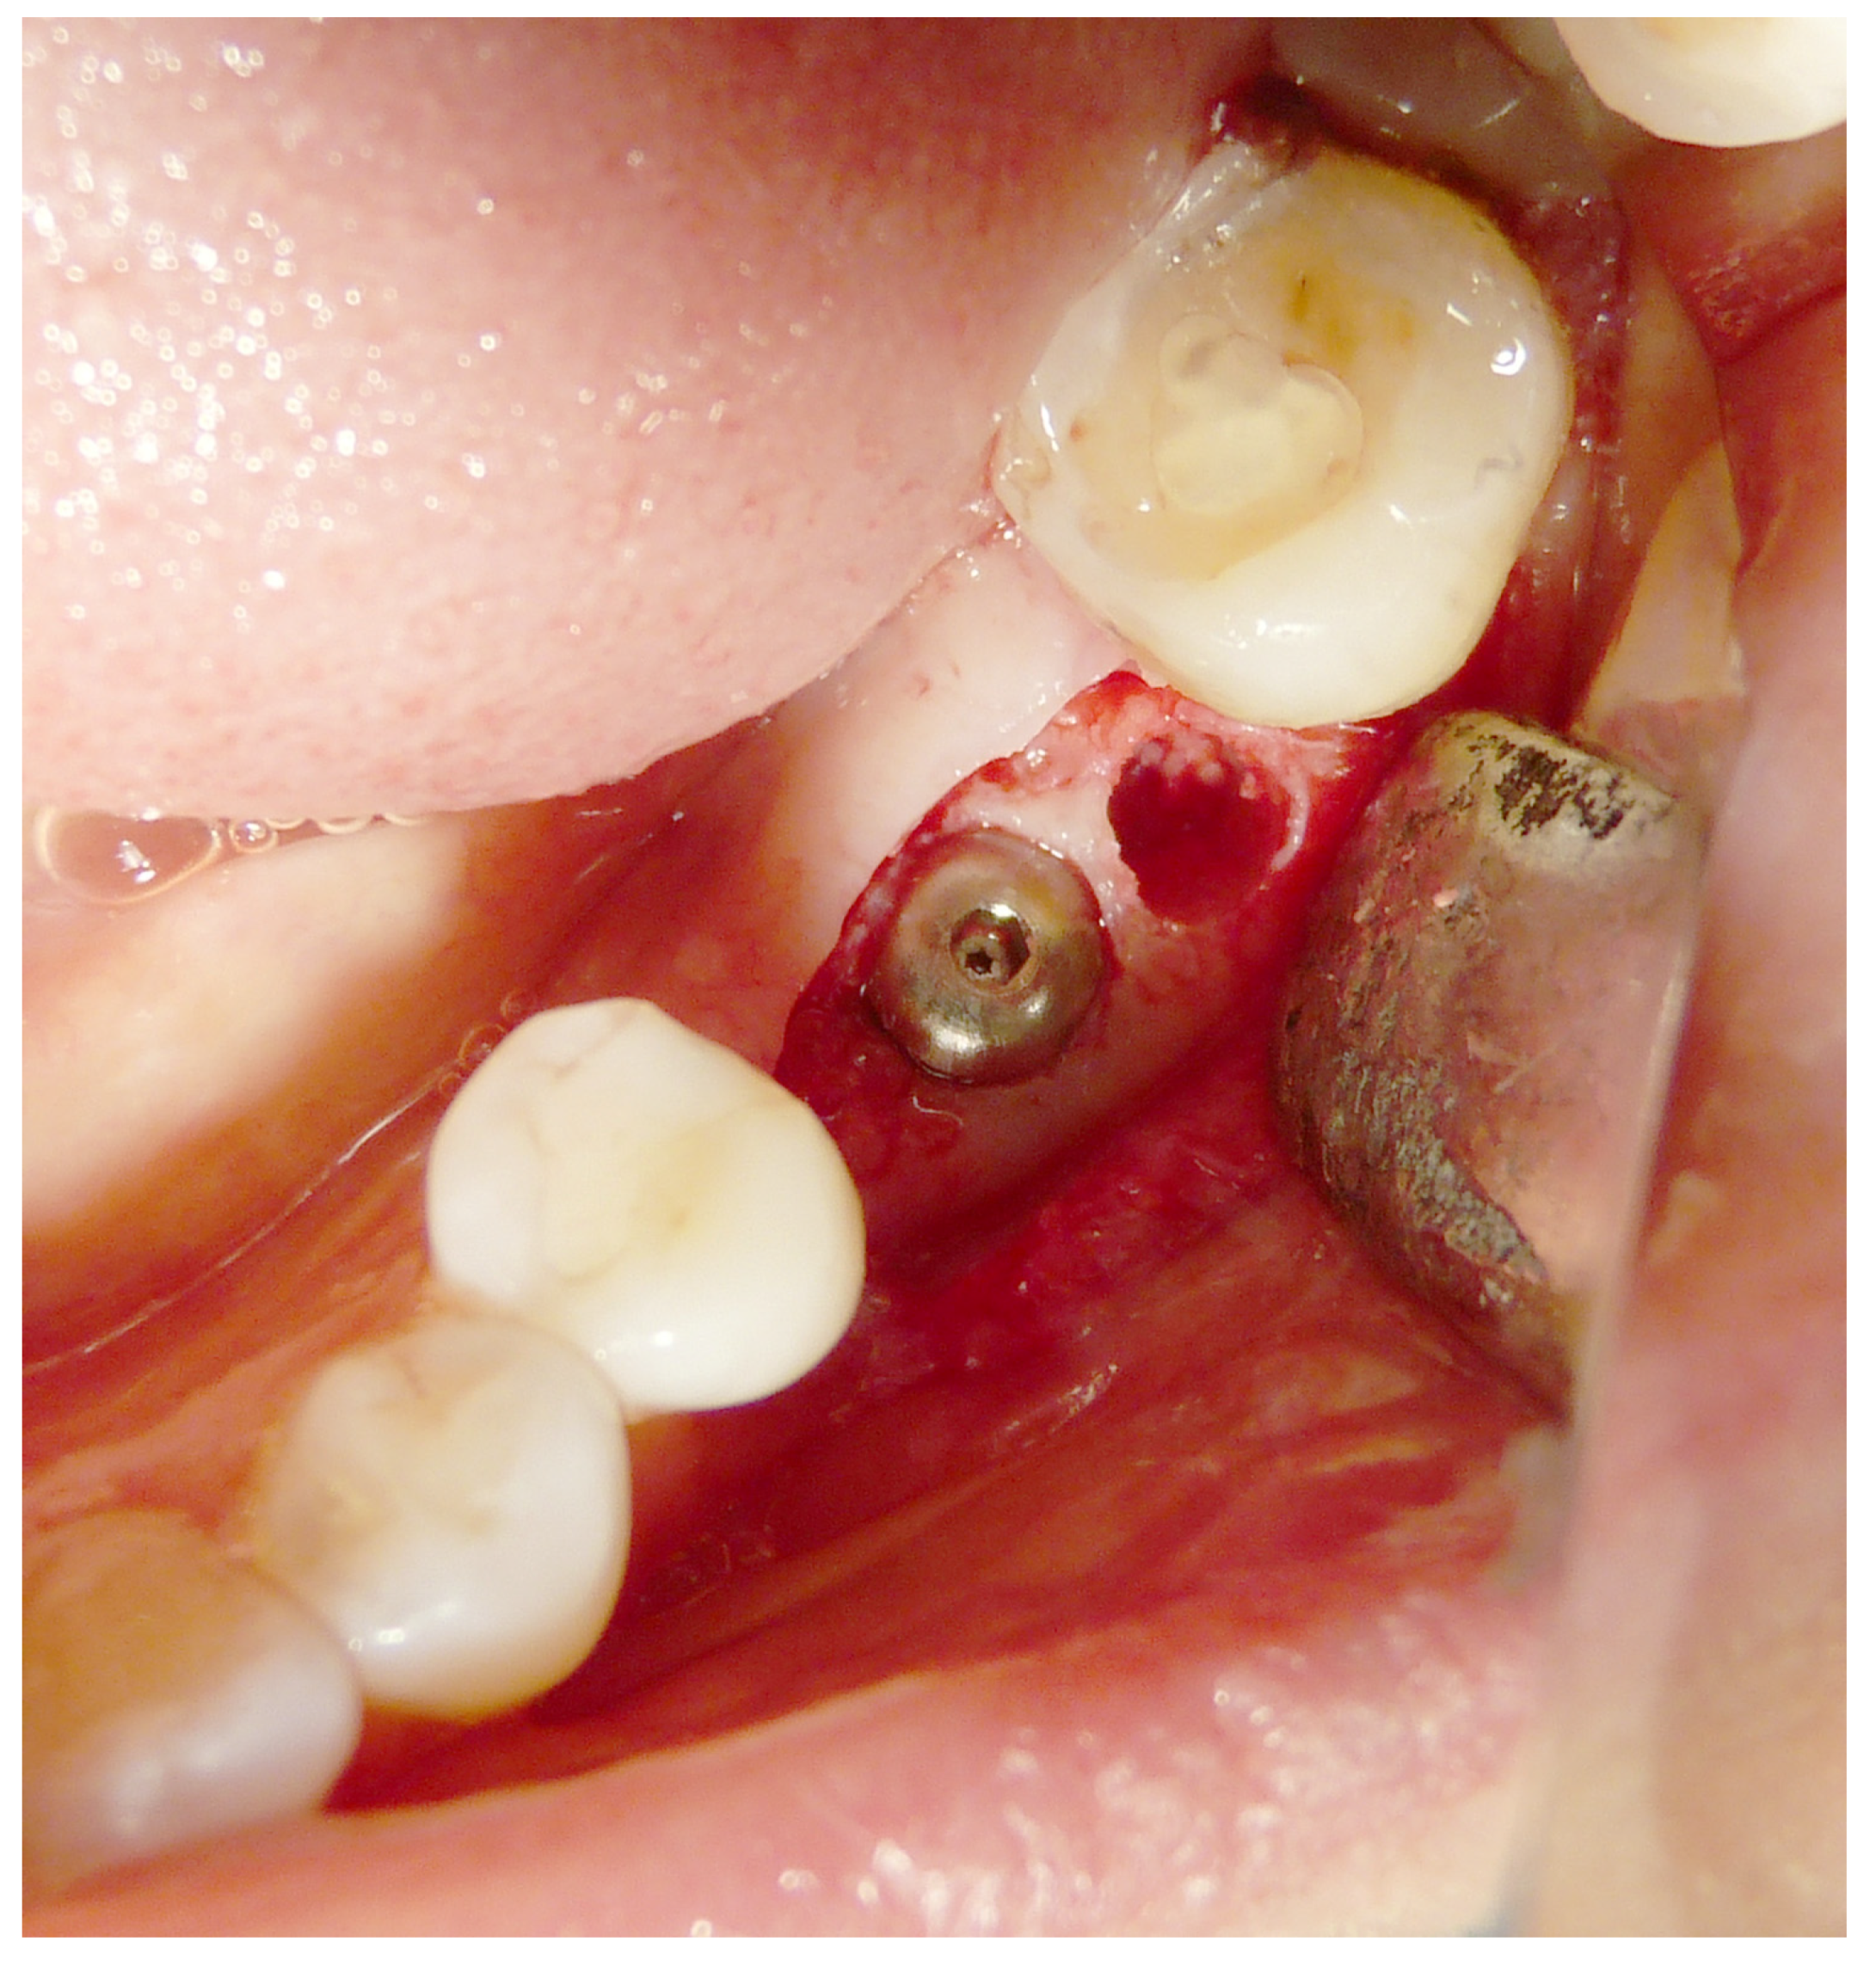

Both hard and soft tissues remained steady throughout the healing process. There were no difficulties with the soft tissue grafting treatments’ healing. After a healing period of 4 months, seven biopsies (Figure 2 and Figure 3) were performed during the implant insertion procedure; after the healing period (8 months after the socket preservation procedure), seven biopsies were performed (Figure 4 and Figure 5).

Figure 4.

Second histology after 8 months of healing.